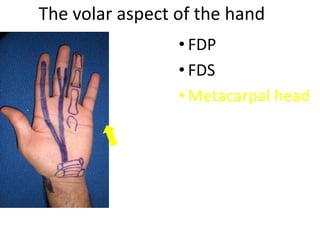

- Naming the bones, joints, tendons, nerves and skin landmarks of the hand and wrist.

- It describes flexor tendon zones, extensor compartments, and pulley system anatomy.